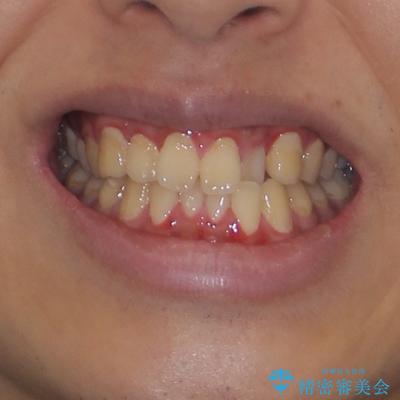

気になっていたクロスバイトは速やかに改善され、1年間で治療を終えることができました。

治療開始前は汚れが多く、全体的に歯肉が腫れていましたが、矯正治療を通して腫れも少しずつ改善されました。